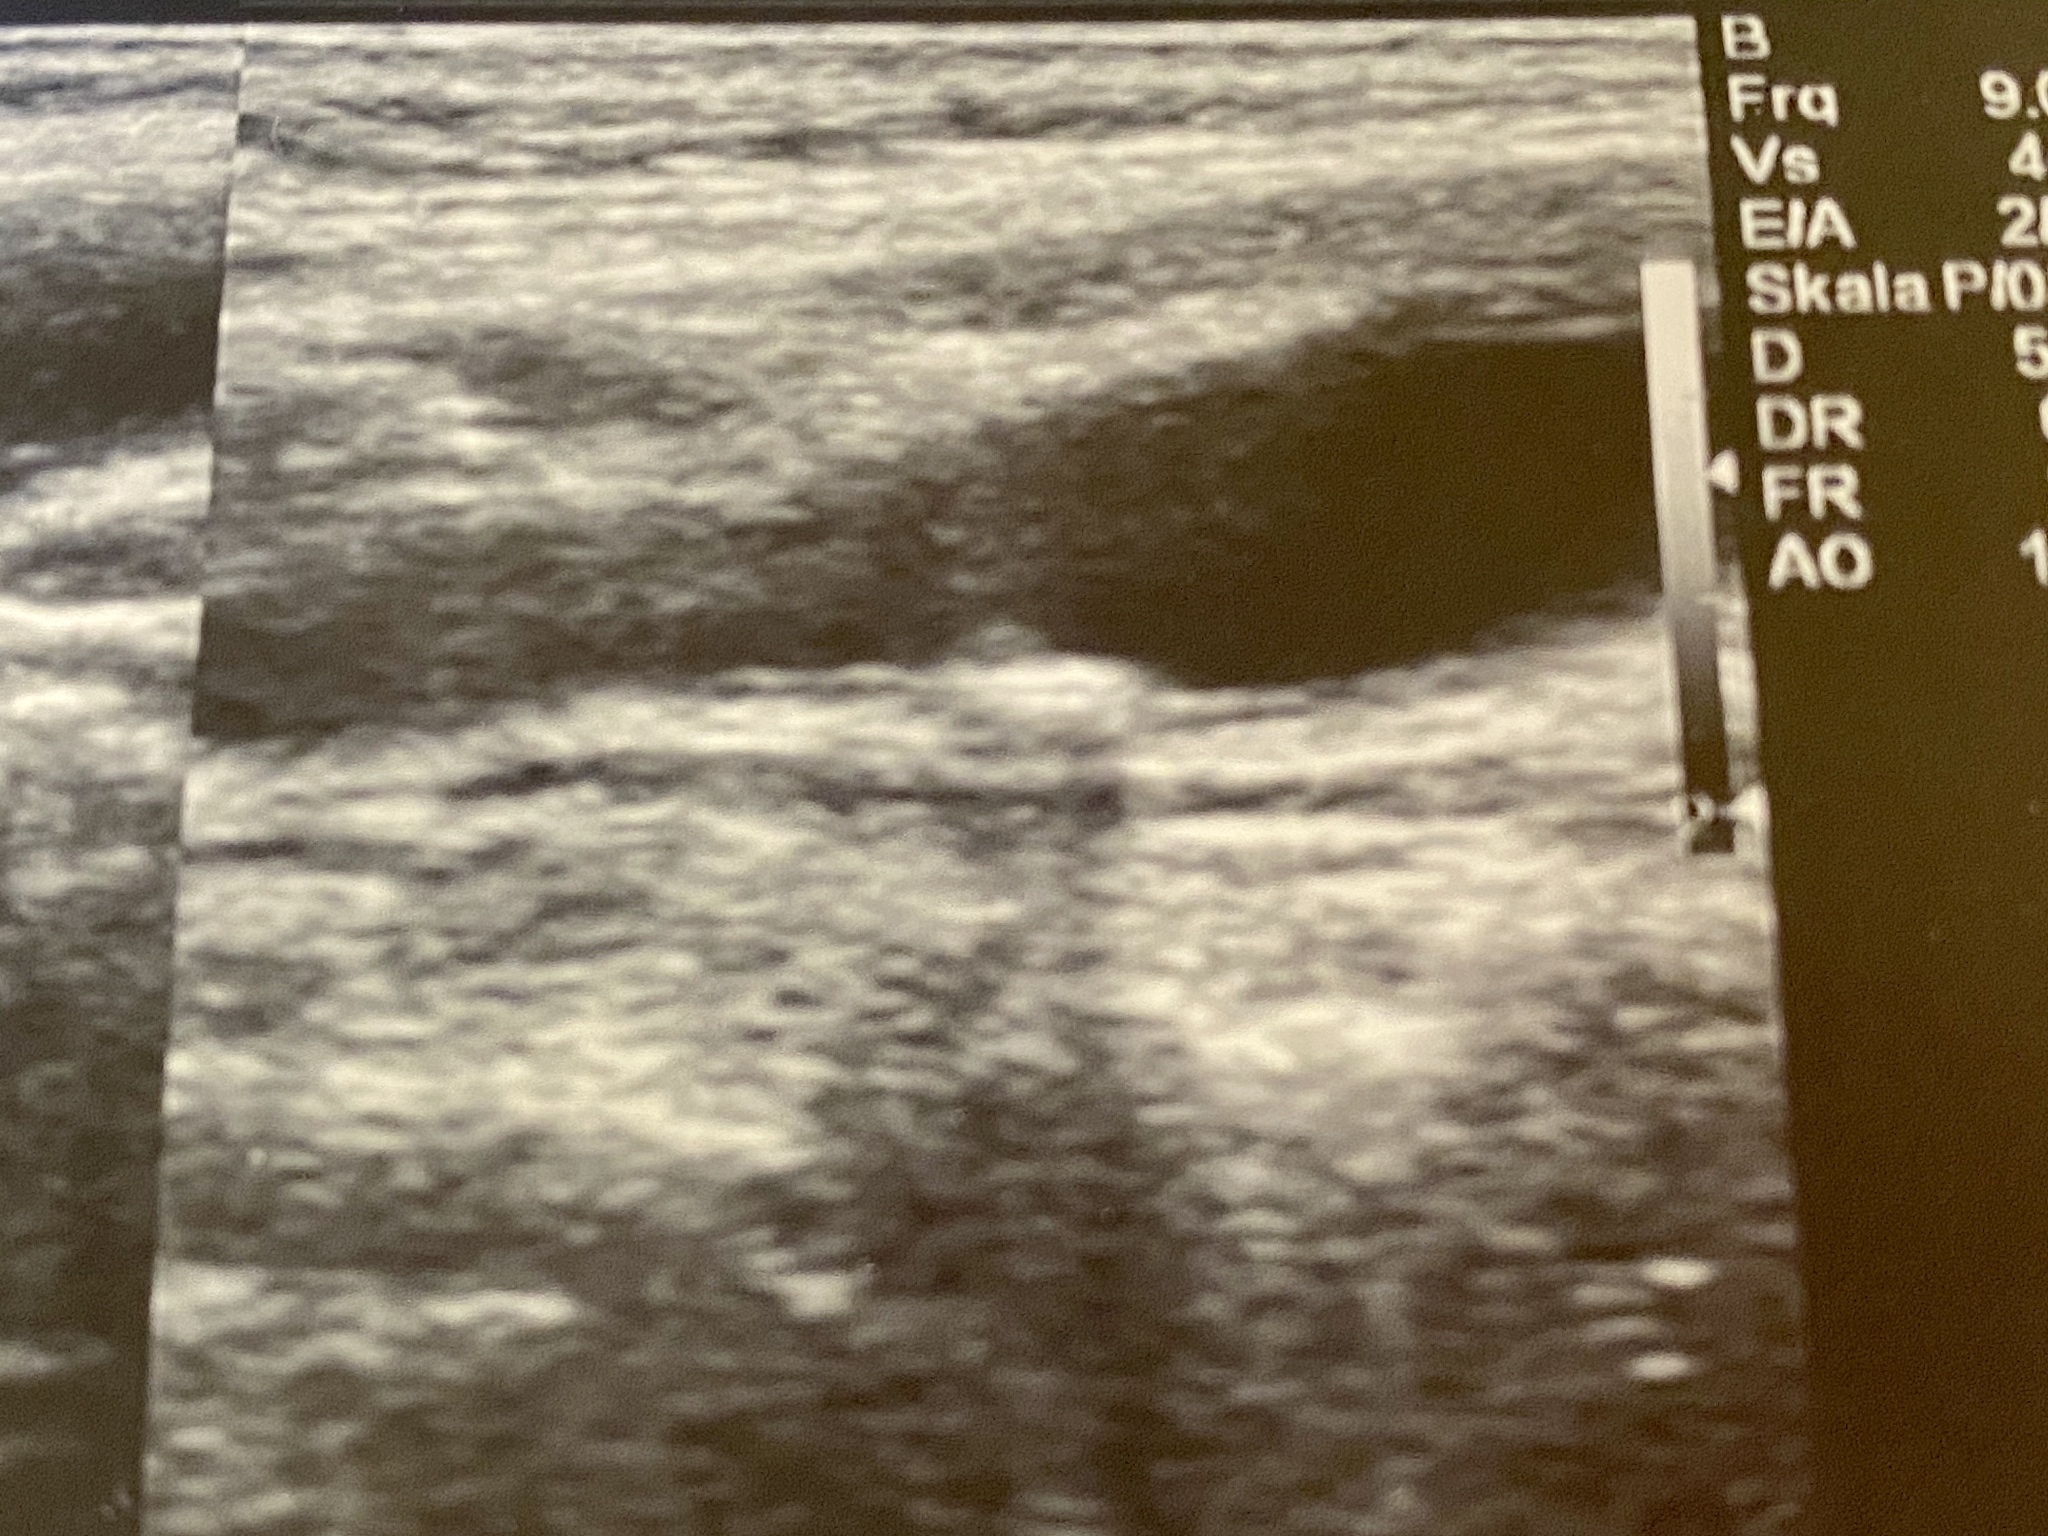

Based on further diagnostic testing, an enhanced ultrasound examination was performed, which showed a slightly hypoechoic plaque with multiple neovascularization within (Figure 1), accompanied by a partial discontinuity of the fibrous cap on the surface of the plaque. The discontinuity was approximately 1.4mm wide and 4.0mm deep, and was filled with contrast agent (Figure 2). At the proximal end of the plaque, there was a low hypoechoic attachment measuring approximately 7.8×3.2mm, which was attached to the vessel wall, while the distal end was free-floating within the lumen of the vessel (Figures 3 and 4). During the contrast-enhanced ultrasound, the low hypoechoic area did not show any enhancement, and there was slight movement observed.

超声检查发现斑块表面纤维帽局部中断,伴随低回声附着物